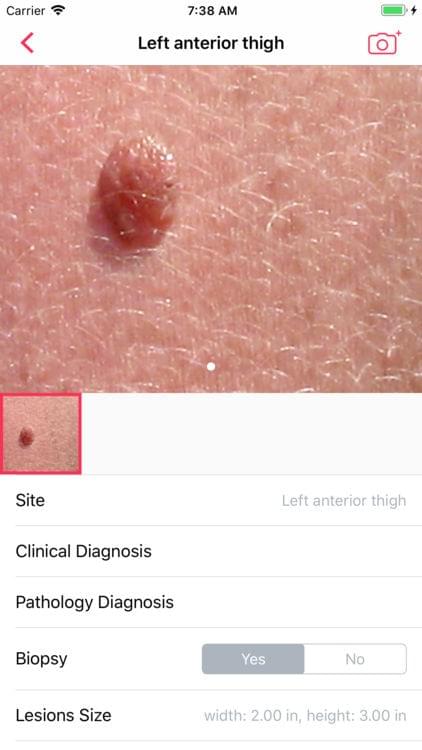

Skin — Image Capture

Skin is a digital health imaging app for tracking of moles and skin lesions. The platform is targeted towards academic researchers, physicians and patients looking to integrate a robust sharing platform for the management and surveillance of dermatological conditions. This app gives medical institutions and physicians a secure option to create scalable studies with hundreds of patient participants. The tool is intended to help support the creation of an intelligent model for the accurate diagnosis of skin diseases.